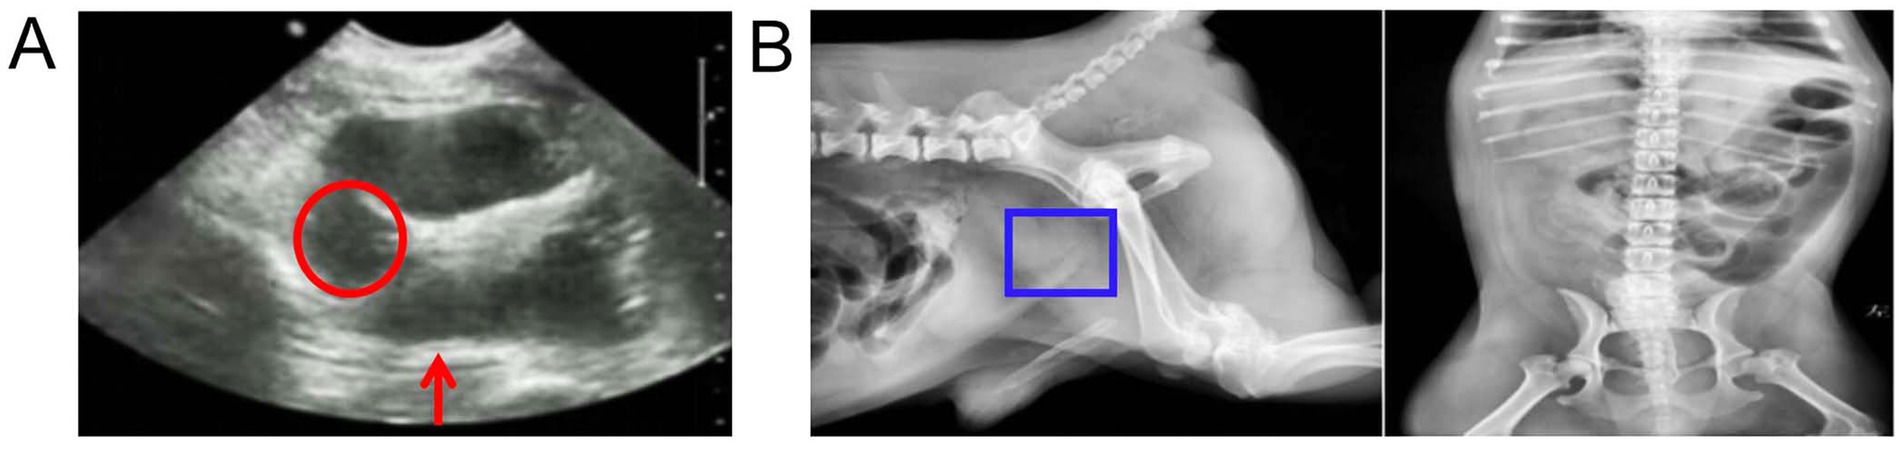

Los resultados ecográficos mostraron que la cápsula prostática era lisa, el contorno era claro, el eco interno no era uniforme, no había eco en el parénquima y el eco estaba realzado en el tejido circundante (Figura 1A). Los hallazgos radiológicos revelaron hinchazón de la región prostática (Figura 1B).